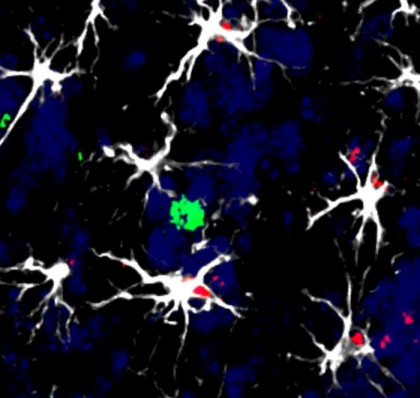

foto: Celulele din jurul unei metastaze cerebrale într-un model animal: mai multe celule cerebrale (astrocite, albe) înconjoară o celulă a sistemului imunitar (limfocite, verde). Unele dintre ele au început să activeze molecula de inducere a factorului (roșu) TIMP1, ceea ce le va permite să dezactiveze acțiunea limfocitelor împotriva celulelor tumorale. Centro Nacional de Investigaciones Oncológicas (CNIO)

Echipa condusă de Manuel Valiente a propus o nouă ipoteză pentru a aborda această problemă. Cercetările lor au arătat că anumite celule din creier, numite astrocite, acționează ca imunomodulatori și pot fi influențate de celulele tumorale în cazul metastazelor cerebrale. Astrocitele pervertite de cancer interacționează cu sistemul imunitar într-un mod care favorizează supraviețuirea celulelor tumorale, împiedicând celulele imunitare să le distrugă.Cercetătorii au identificat o moleculă cheie în acest proces, numită TIMP1. Astrocitele pro-tumorale produc TIMP1, care interferează cu activitatea celulelor imunitare, făcându-le mai puțin eficiente în combaterea cancerului. Astfel, TIMP1 poate servi ca biomarker pentru a detecta metastazele cerebrale afectate de acest mecanism imunodepresor.